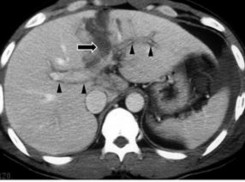

Hình 1.12: Tổn thương tĩnh mạch cửa trên phim CLVT (mũi tên).

Nguồn: Shanmuganathan K, Mirvis SE [21].

- Tổn thương tĩnh mạch gan: Nếu đường vỡ gan đi ngang qua hoặc tiếp cận các tĩnh mạch gan thì nhiều khả năng các tĩnh mạch bị tổn thương [26].

- Tổn thương tĩnh mạch cửa: có thể hiện bằng hình ảnh một thùy hay nhiều thùy gan mất cấp máu. Chụp CT có cản quang cho thấy các vùng gan có tỷ trọng thấp xung quanh tĩnh mạch cửa và các nhánh của nó.